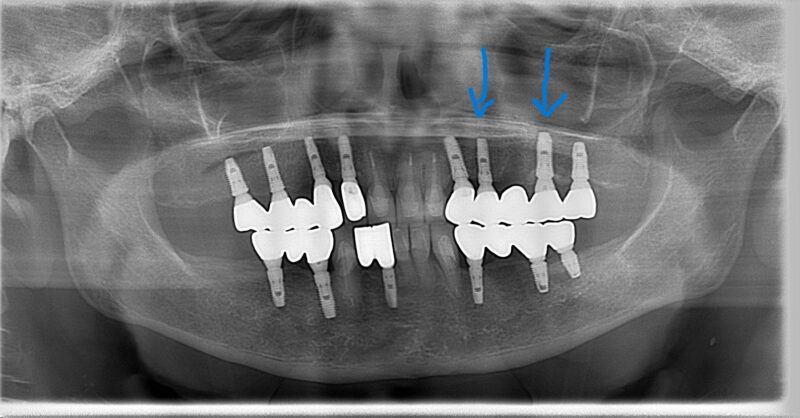

*術後写真 両サイドのインプラントを利用してインプラントブリッジ(2回)

これがインプラント治療の大きなメリットの一つです。天然歯が失われても、既存のインプラントを土台として、新しいブリッジを作製することができるのです。大掛かりな手術を追加することなく、機能的で審美的な治療が可能になりました。

他の部位のインプラントもレントゲンで詳しく確認しましたが、10年間、全く問題のない状態を維持していました。これは適切な治療計画、精密な外科処置、そして患者様ご自身の優れたセルフケアと定期メインテナンスの賜物です。